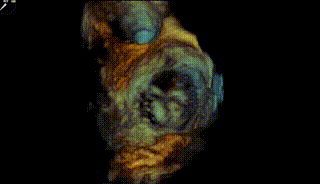

图1-4. 术前在交界、左室长轴切面及3D视角下可见大量二尖瓣反流,反流区宽,MultiVue下可见P2-P3脱垂

【二尖瓣相关参数】二尖瓣关闭时P2P3呈弓形脱入左房。二尖瓣后叶脱垂并重度偏心性反流(原发性:Carpentier II型,缩流颈8.3mm,反流面积0.42cm²,反流容积71ml);P2+P3区脱垂,脱垂范围约14×10mm,前叶2偏3区瓣体长度:25mm,后叶2偏3区瓣体长度:19mm;MVA:6.33cm²。左房内径47mm,左室60/39mm。